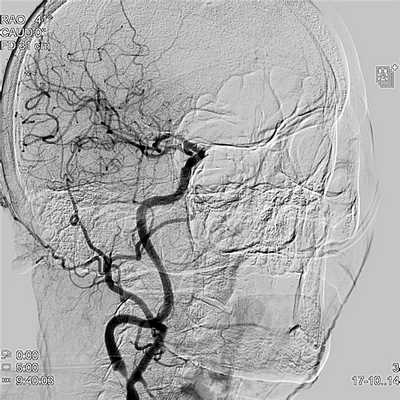

Ангиография магистральных артерий головы

Каротидная ангиография является инвазивной рентгеновской процедурой визуализации сонных артерий, которая проводится через катетер введенный в кровеносный сосуд на руке или ноге. Через катетер вводится контрастное вещество которое непрозрачно для ренгеновских лучей и поэтому показывает внутренний просвет сонных артерий. Эта процедура является "золотым стандартом" для визуализации сонных и церебральных сосудов.

Ангиография сонных артерий в Инновационном сосудистом центре

В нашей клинике каротидная ангиография является заключительным методом диагностики перед проведением эндоваскулярного лечения патологии сонных или позвоночных артерий. Учитывая, что исследование имеет хоть небольшой, но все же риск развития неврологических осложнений, его не используют для скриннинговой диагностики. Для этого в нашей клинике используются другие методы визуализации (УЗИ сонных артерий, МСКТ - ангиография).

Как проводится исследование

В операционной медсестра устанавливает внутривенный катетер, для того, чтобы вводить необходимые лекарства во время исследования. Пациент укладывается на специальный рентгенпрозрачный стол. Медсестра обрабатывает кожу в месте доступа специальным антисептическим раствором, после чего операционное поле накрывается стерильной простыней. На груди будут размещены электроды, которые соединяются с монитором давления и электрокардиографии. Это необходимо для контроля над функцией сердца во время исследования.

Вам могут дать легкое успокоительное, но вы будете в сознании во время всей процедуры. Врач проведет местное обезболивание, чтобы вызвать онемение участка для пункции в паховой области или в области запястья. После пункции устанавливается тонкий проводник, по которому проводится пластиковый интродьюсер (короткая трубка, через которую проводится доступ в артерию). Через интродьюсер проводится длинный проводник и катетер к устью сонной артерии.

Через катетер подается контрастное вещество в исследуемую сонную артерию. Контрастное вещество очерчивает сосуды и позволяет выявить патологию сонных артерий.

Во время исследования врач может попросить задержать дыхание или повернуть голову в разных направлениях. После достижения целей исследования катетер извлекается. Место доступа в артерии закрывается специальным сшивающим устройством и накладывается давящая повязка. Пациент переводится в палату.